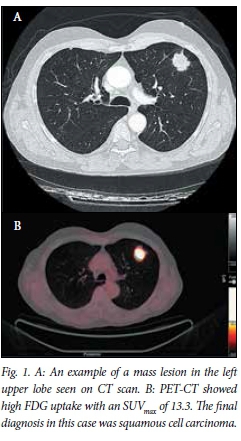

Chest radiograph and CT findings

The average diameters of the lesions measured were 29 mm in the vertical axis and 30 mm in the horizontal axis on standard anteroposterior (AP) chest radiograph, and these were very similar to the CT measurements (Figs 1 and 2). Lesions ultimately proven to be malignant were most frequently observed in the right (n=12) and left upper lobes (n=8).

PET-CT findings and SUVmax